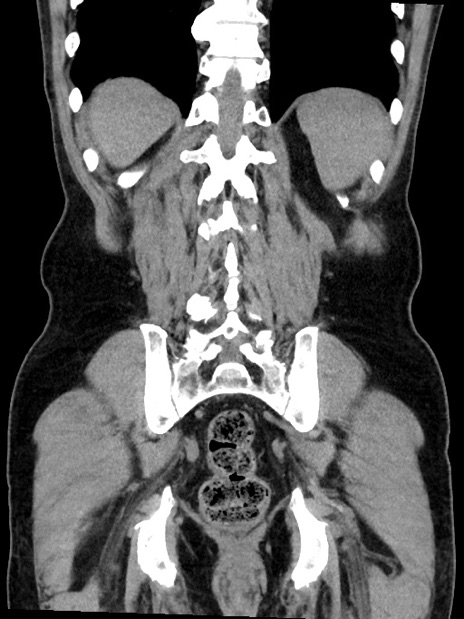

症例35(冠状断像)

症例

【症例】70歳代 男性

【主訴】腹部膨満、嘔吐

【現病歴】昨日より腹部膨満感出現。本日増悪し、仙痛出現。嘔吐あり、受診。

【既往歴】糖尿病、胆摘後

【身体所見】BP 149/80mmHg、HR 74/min、BT 35.9℃、腹部:膨満、軟、圧痛なし。腸雑音減弱あり。上腹部正中切開瘢痕あり。

【データ】WBC 13500、CRP 1.72